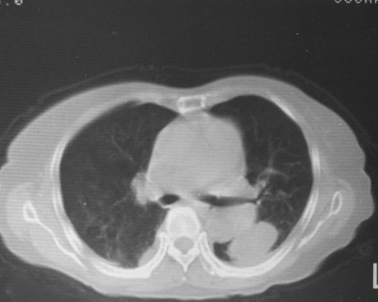

女,80岁,10天前胸片示双下肺感染,正规治疗后复查。体温不高,有脓痰,无臭味。

左下肺片状及块状密度增高影,其内见液化密度影及充气支气管影.考虑炎性病灶,肺脓肿形成

左肺下叶大部实变,内可见含气支气管征。后部见长椭圆形低密度区,周围坏一薄壁。

考虑:左下肺炎症,包裹性胸腔积液。

支持:左肺下叶大部实变,内可见含气支气管征。后部见长椭圆形低密度区,周围环一薄壁,局部胸膜增厚。结合病史考虑:左下肺炎症,包裹性胸腔积液。

考虑:左下肺炎症,包裹性胸腔积液